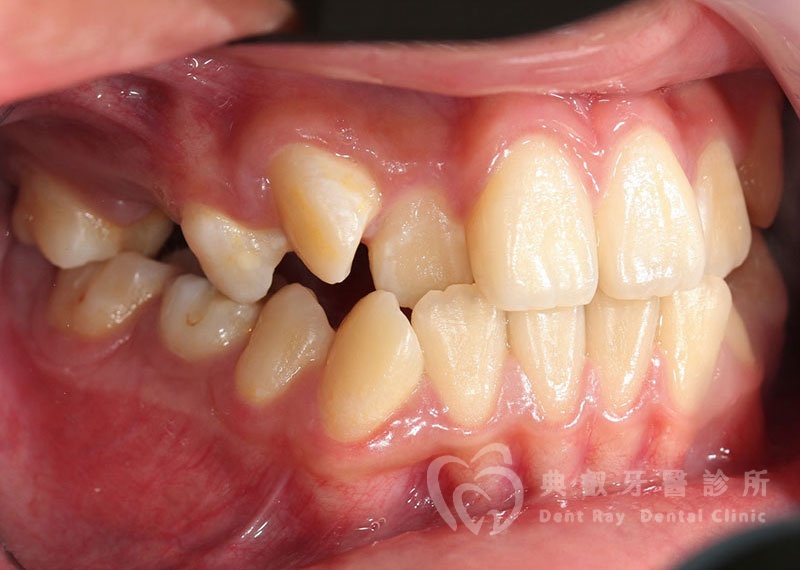

排列擁擠案例一

Before

After